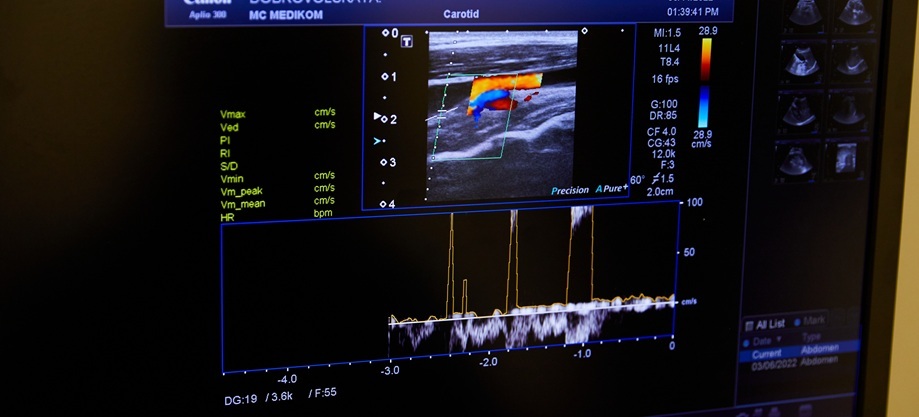

УЗИ мягких тканей (эхография) — это диагностика подкожной клетчатки, мышц, сухожилий, фасций, сосудов с помощью ультразвука. От датчика УЗ-системы устремляются безопасные ультразвуковые волны, которые отображаются от разных тканей по-разному и превращаются компьютером в изображение в реальном времени. Потому доктор может рассмотреть все структуры и ткани, которые видны на УЗИ, без вмешательства в организм. Специалисты отмечают: благодаря этому методу проблемный участок можно исследовать с разных ракурсов, при сгибании и разгибании конечностей, сокращении мышц, что позволяет получить максимум ценной информации.

Возможности метода ультразвуковой диагностики расширяются за счет дополнительного режима — доплерографии, с помощью которой исследуется кровотечение. Это имеет очень важное значение, в частности, в диагностике новообразований.

- Современные аппараты УЗИ с режимом доплерографии для тщательного обследования мягких тканей.